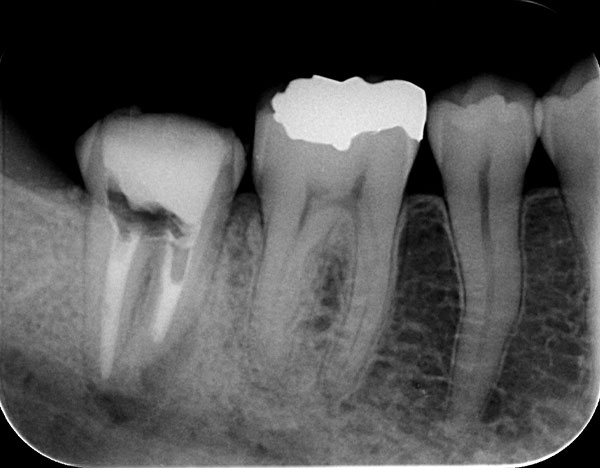

• 治療前

• 治療後

他院にて抜歯と診断され、当院に来院された患者様。根尖病巣が大きく、歯茎から膿が出ている状態でした。歯の根っこが強く曲がっており、根管治療での改善はみられなかったので、口腔外にて逆根管充填を行い整復した症例です。術後2ヶ月ですが、現在、症状もなく治癒傾向にあります。

他院にて根管治療を受けているが症状の改善がみられず、歯茎の腫れも引かないため当院を受診された患者様です。無菌的処置を行い、封鎖性の高い根管充填剤を用いることで症状は改善し、術後3か月後のCTで根尖病巣の縮小を認めました。根管治療は2回で終了しています。